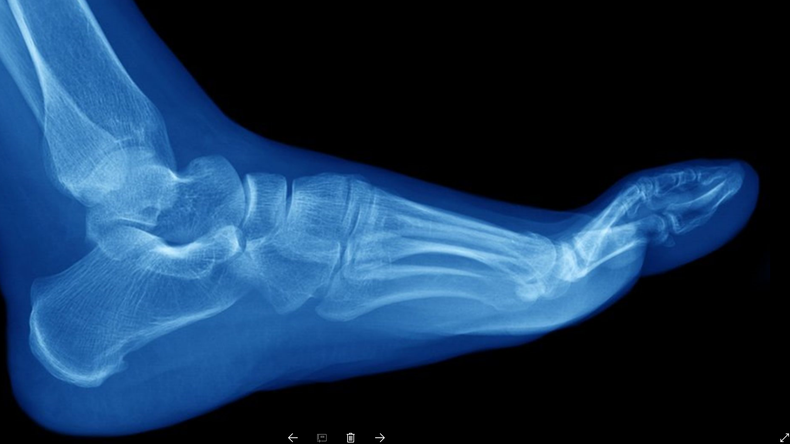

Las fracturas de hueso que la mayoría de la gente conoce son debidas a un golpe traumático. Pero hay otro tipo de lesiones, llamadas fracturas por estrés, por esfuerzo o por fatiga, en las que se generan pequeñas roturas o micro traumatismos en los huesos debido al impacto repetitivo del sobreuso.

Este tipo de roturas están normalmente asociadas al deporte y suelen ocurrir en los huesos de la parte inferior de la pierna y el pie, como la tibia y el peroné, los metatarsos, el talón y el tobillo.